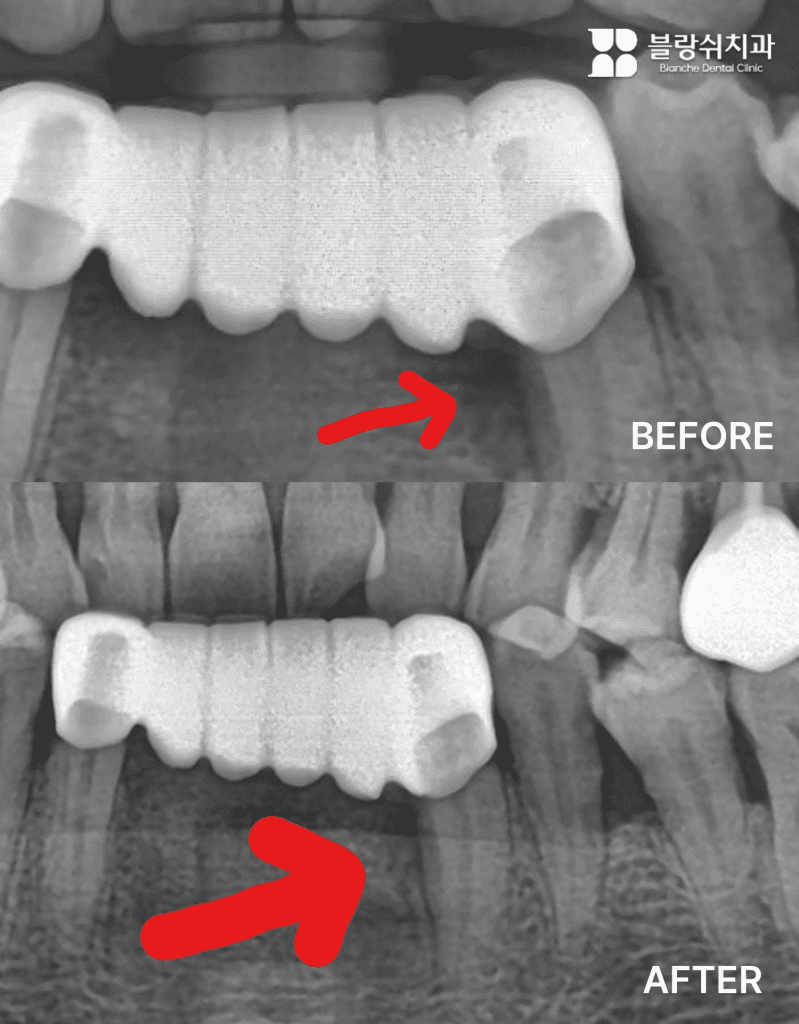

• 진단: 파노라마 엑스레이에서 잇몸뼈가 수직으로 깊게 내려간 형태의 골소실이 관찰되었습니다.

• 판단 포인트: 중요한 건 뼈가 녹았다는 사실보다 어떤 형태로 녹았느냐입니다. 수직 결손은 재생 치료의 타겟이 되기 쉬운 편이에요. 치아 흔들림이 일부 있었지만 살릴 가능성이 있다고 판단했습니다.

• 치료: 엠도게인 도포 + 뼈이식 병행으로 진행했습니다.

• 결과: 11개월 후(2023년 1월 → 2023년 12월) 엑스레이 비교에서 잇몸뼈가 차오른 모습이 확인되었습니다.